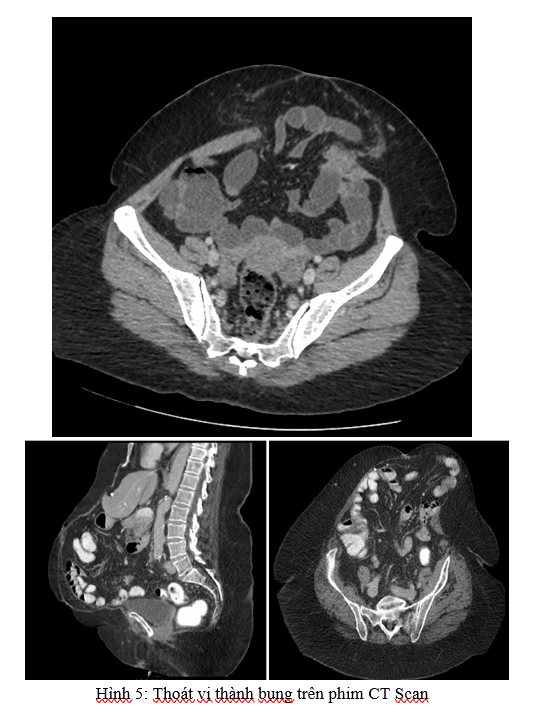

- CT scan:

• Đánh giá chính xác vị trí, kích thước túi thoát vị, tạng và tính chất tạng thoát vị, đường kính lỗ thoát vị, tình trạng cơ thành bụng… Từ đó đưa ra kế hoạch điều trị phù hợp.